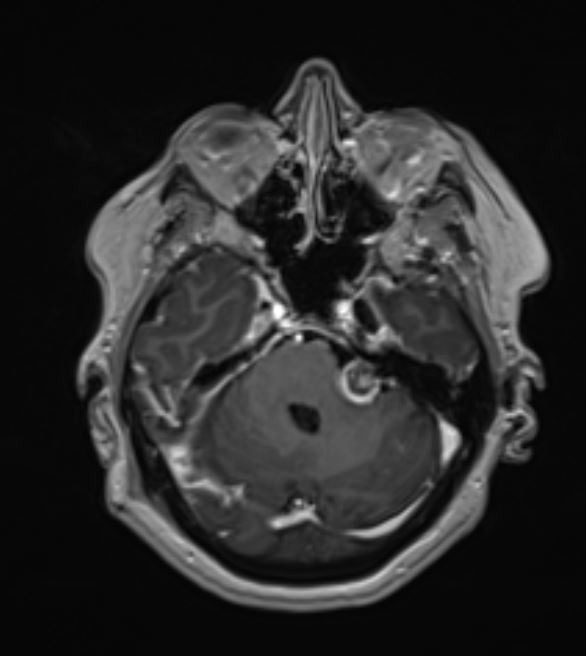

Η μετεγχειρητική μαγνητική τομογραφία ανέδειξε πλήρη εξαίρεση του όγκου (βλ εικόνες).

Το μεγαλύτερο τμήμα του όγκου προσπελάσθηκε μέσω μιας τυπικής οπισθοσιγμοειδικής κρανιοτομίας όμως πρόβλημα αποτελούσε το τμήμα του όγκου το οποίο επεκτείνονταν στην περιοχή του γαγγλίου. Προκειμένω να αφαιρεθεί και αυτό το κομμάτι του όγκου “ανοίξαμε” την κορυφή του λιθοειδούς αφαιρώντας το οστικό έπαρμα ύπερθεν του εσω ακουστικού πόρου, μια απαιτητική και ιδιαιτερη τεχνική. Έτσι καταφέραμε την ολική εξαίρεση της βλάβης και την απαλλαγή της ασθενούς από τα συμπτώματά της.